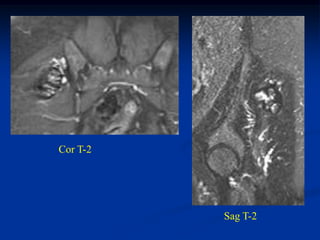

Case #1211.2               Synovial hemagioma knee

15 year male with knee pain for 6 months

Coronal T-1   Coronal T-2

Axial T-2

Surgical exposure at time of excisional biopsy

Case #1211.2 Synovial hemagioma knee 15 year male with knee pain for 6 months

• 363.

• 364.

• 365.

Surgical exposure attime of excisional biopsy